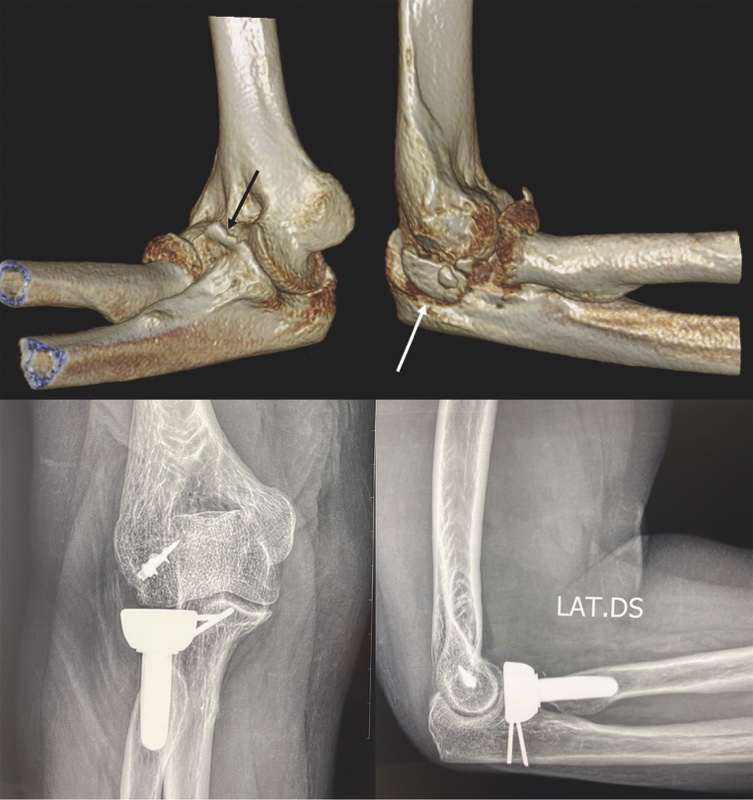

Osteosintesi della coronoide

Le piccole fratture dell’apice coronoideo che non includono l’inserzione capsulare possono non essere trattate chirurgicamente. Quando l’osteosintesi di un piccolo frammento coronoideo non è tecnicamente possibile, è consigliato eseguire una capsulodesi anteriore mediante un’osteosutura per incrementare la stabilità del gomito. Nelle fratture con frammenti di maggiori dimensioni, è possibile eseguire l’osteosintesi con fili filettati retrogradi (Fig. 1) o viti a compressione. Nelle fratture pluriframmentarie di tipo 3, può essere necessario associare la sintesi con placca per via mediale.

Nel gomito instabile, in cui sono presenti lesioni legamentose, è fondamentale rispristinare la funzione del capitello radiale (stabilizzatore secondario) per garantire la congruenza articolare e proteggere le strutture riparate (legamenti) durante i processi di guarigione. Per questi motivi è sconsigliato eseguire la sola capitellectomia. Nel caso di fratture marginali (<20%) è possibile eseguire solo l’escissione dei frammenti quando non sono sintetizzabili. Nel caso di fratture che coinvolgono la circonferenza radiale (Mason II), in cui i frammenti non risultano comminuti, è possibile eseguire l’osteosintesi con viti libere senza testa. Nel caso di fratture con affondamento della giunzione testa-collo è necessario risollevare la testa ed eseguire l’osteosintesi con placca dedicata. Nelle fratture pluriframmentarie “whole head”, quando i frammenti appaiono ricostruibili, è possibile eseguire l’osteosintesi con placca, con o senza l’aggiunta di viti libere interframmentarie. In tutte le fratture non ricostruibili è necessario eseguire la sostituzione protesica (Fig. 2).